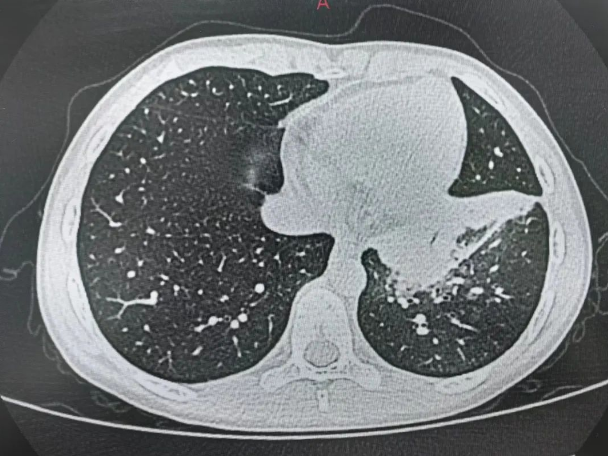

【首儿医典】儿童支原体肺炎